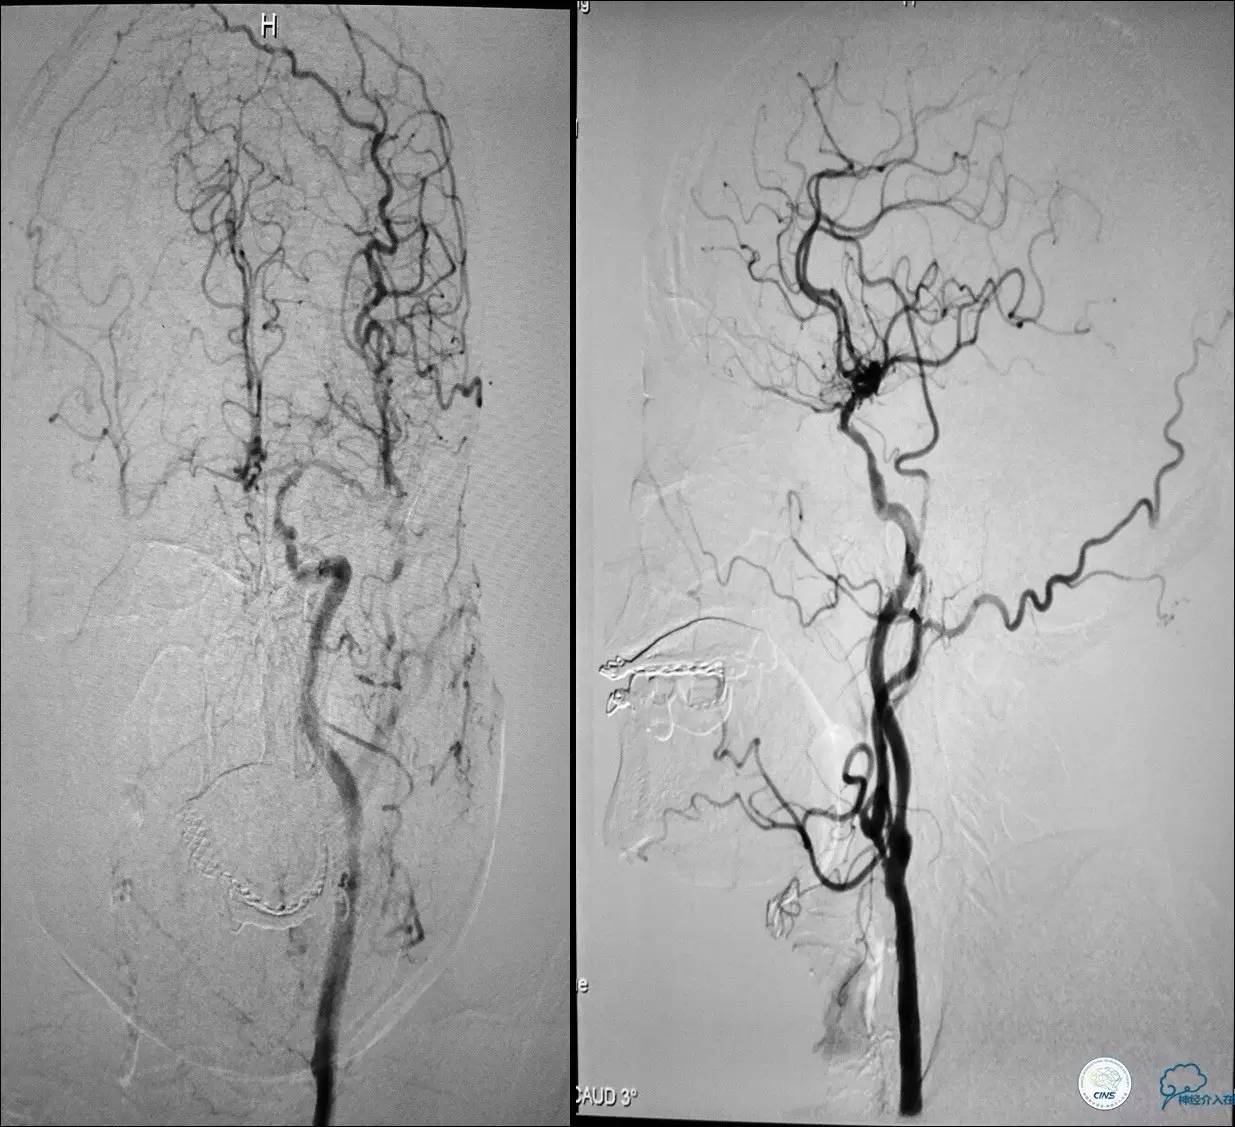

》男,79岁。

》主诉:阵发性头晕伴双下肢无力一年余。

》查体:左侧上肢肌力Ⅱ级, 双侧下肢肌力Ⅲ级。

》既往史:高血压、糖尿病史。

》术后严密控制血压,未出现明显血压波动。

》术后三小时,患者出现恶心呕吐,伴有意识丧失。

》出血原因?侧支代偿不佳!

颈动脉次全闭塞 术前评估

》头颅灌注+DSA!

头颅灌注: 注意两侧CBF CBV的对比。

DSA:注意侧支代偿。